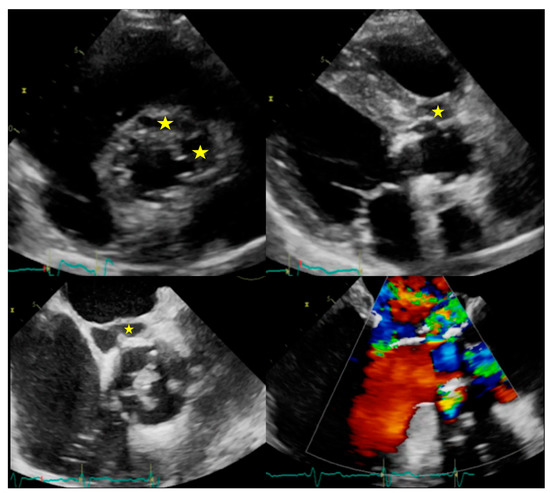

5.2. When to Ask for TTE and When to Ask for TOE

5.3. Role of CCTA in Diagnosing IE and Local Complications

| Right-sided IE | TTE generally provides good visualization of tricuspid valve. TOE is useful in the assessment of IE related to CHD. | Pulmonary valve is difficult to assess. | ||||||||